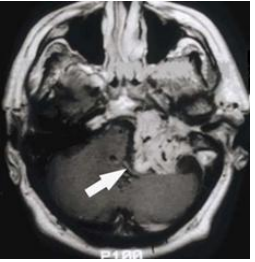

73 53 歲女性病人,主訴聲音沙啞、吞嚥困難、脈衝性耳鳴(pulsatile tinnitus)和聽力減退,接受磁振 造影檢查(MRI),下圖為注射顯影劑後的 T1 加權影像,圖中箭頭所指病灶最可能的是:

(A)頸靜脈球瘤(glomus jugulare) (B)脊索瘤(chordoma) (C)神經鞘瘤(schwannoma) (D)多型性神經膠母細胞瘤(glioblastoma multiforme)